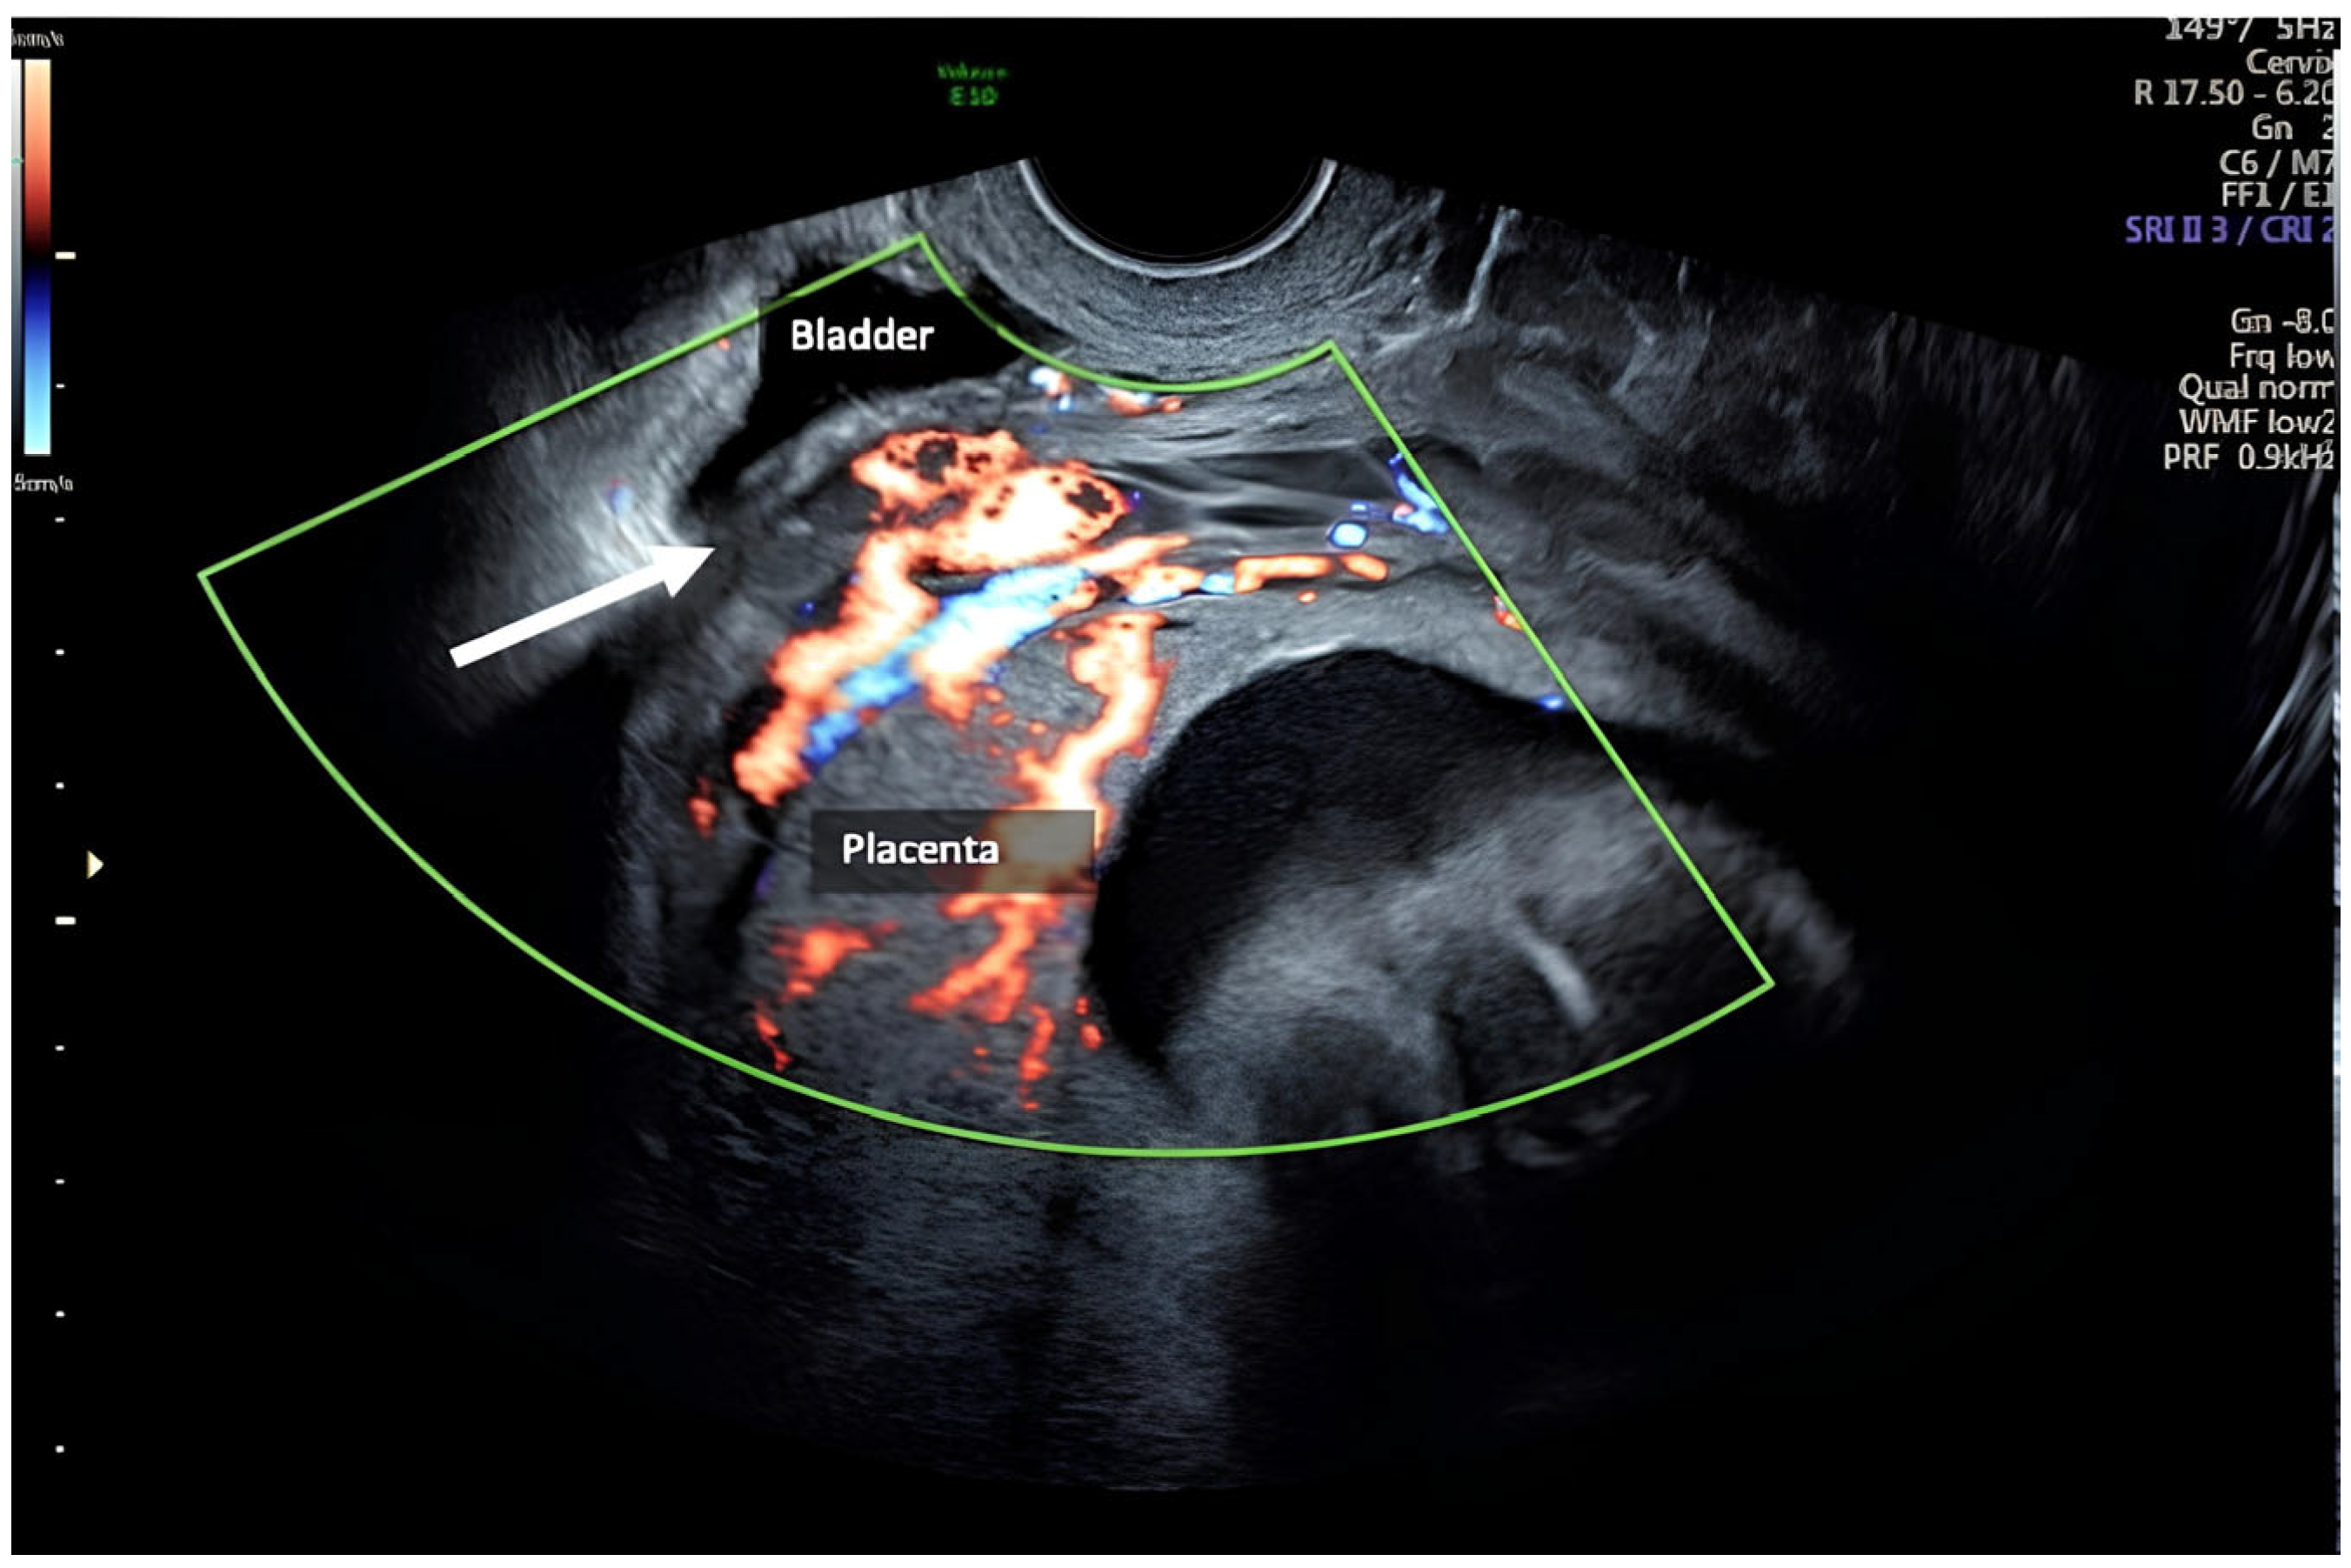

| Zermano S. et al. | 2024 | 29 1/7 | No | Yes | Yes | Yes | |